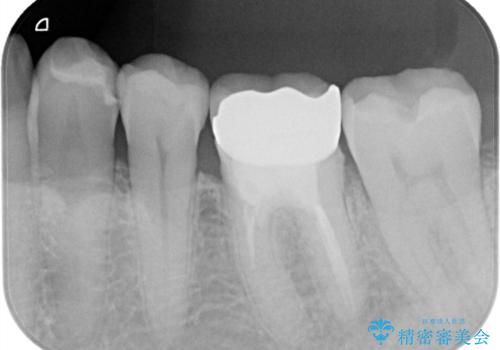

拡大鏡下で丁寧に虫歯を取り除き、セラミックインレーによる修復治療を行いました。

銀歯を固着するセメントは経年劣化し溶け、隙間ができます。そこにプラークが侵入して虫歯が再発します。今回のように銀歯が脱離してしまうこともあります。

今回は銀歯が取れたので、虫歯が神経まで達して痛みが出る前に、強度・審美に優れ、虫歯の再発の少ないセラミックインレーにて治療を行うことができました。